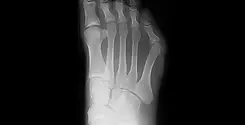

外反母趾(がいはんぼし)

外反母趾とは、親指が人差し指側に「く」の字状に曲がった状態の事をいいます。

原因は様々で必ずしもヒールをはいたから発症する病気ではありません。

遺伝的影響として、足の形や足趾間の靭帯・筋肉の緩みや弱さなどによる軟部組織のアンバランスなども考えられます。